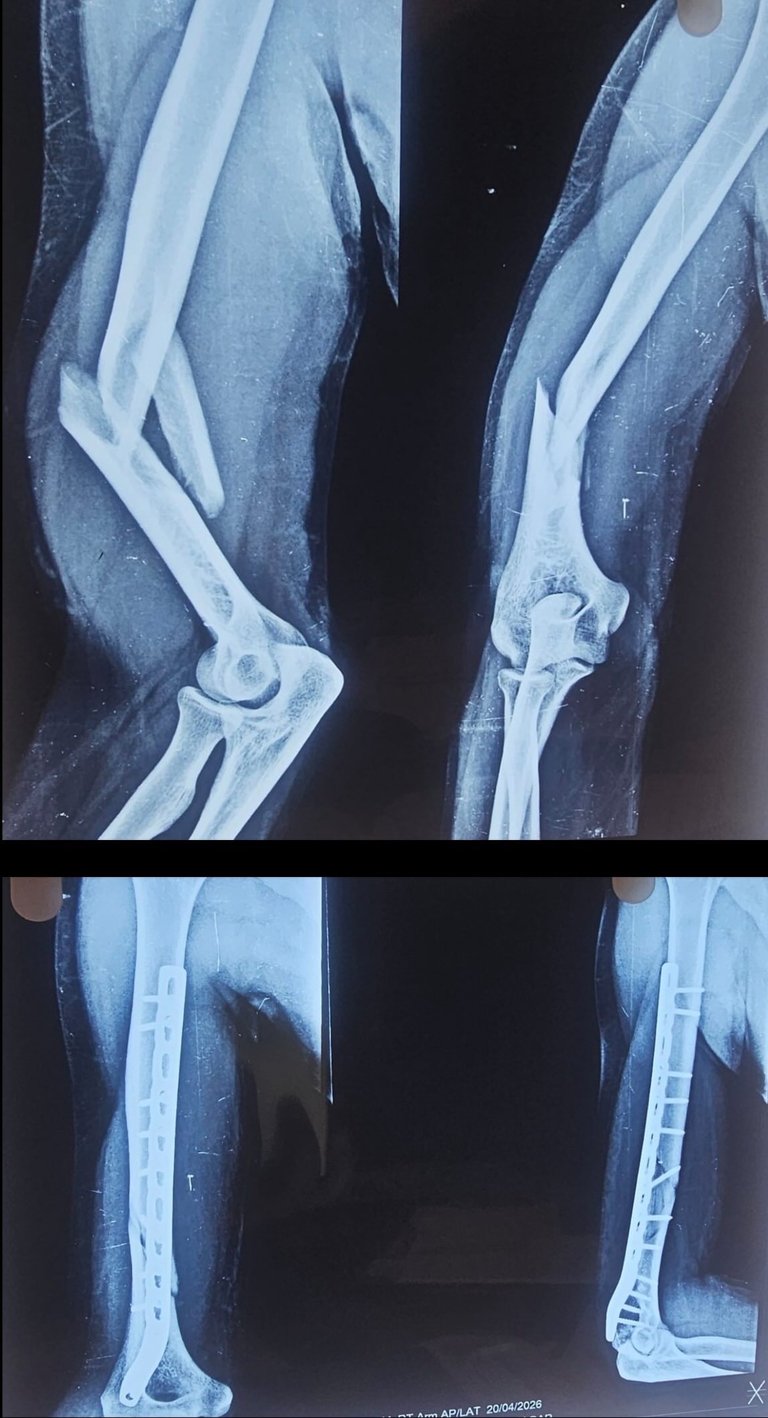

Fractures

Expert surgical care for complex and open bone fractures to restore strength.

Revisions

Correcting previous surgeries and healing stubborn non-union fractures with precision.